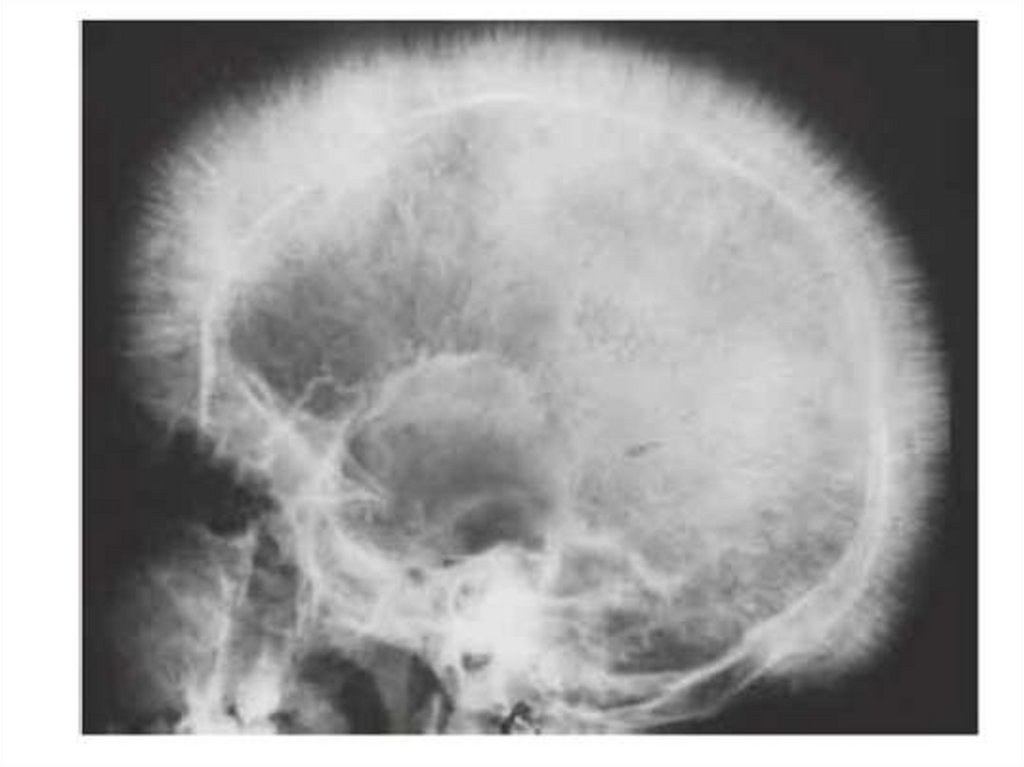

Костный мозг при В12 -дефицитной анемии

Преобладают

эритромегалобласты с

задержкой созревания

ядра.

В препарате гигантские

палочкоядерный и

полисегментарный

нейтрофилы.